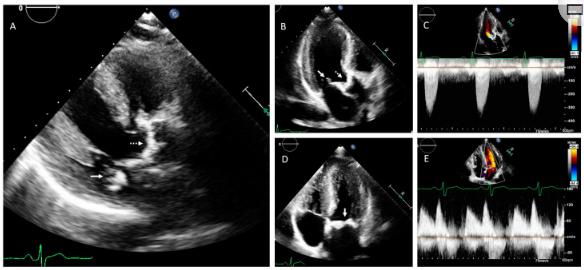

对该家族的调查显示,先证者的兄弟姐妹分别在38岁和40岁时(图4、II1–II3)和他们的父亲(图4、I1)患有心脏瓣膜病。父亲(图4、I1)也患有主动脉瓣和二尖瓣狭窄,为此在55岁时进行了主动脉瓣置换术。左心室尺寸正常。姐姐(图4、II.1)和其中一个兄弟(图4、II.2)也具有主动脉瓣和二尖瓣狭窄,并伴有左心室向心性肥大。弟弟的超声心动图图像显示在图5A–E .根据现有超声心动图数据或该家族成员的临床表现,没有迹象表明瓣膜性心脏病的风湿性病因。

图5、家族2中II2的经胸超声心动图检查显示主动脉瓣狭窄和二尖瓣钙化。(A)胸骨旁长轴位,(B)顶三腔位,(C)主动脉瓣上连续波多普勒显示主动脉钙化和狭窄(虚线箭头)。(D)尖顶4室视图,(E)二尖瓣连续波多普勒,显示二尖瓣钙化和狭窄(连续箭头)